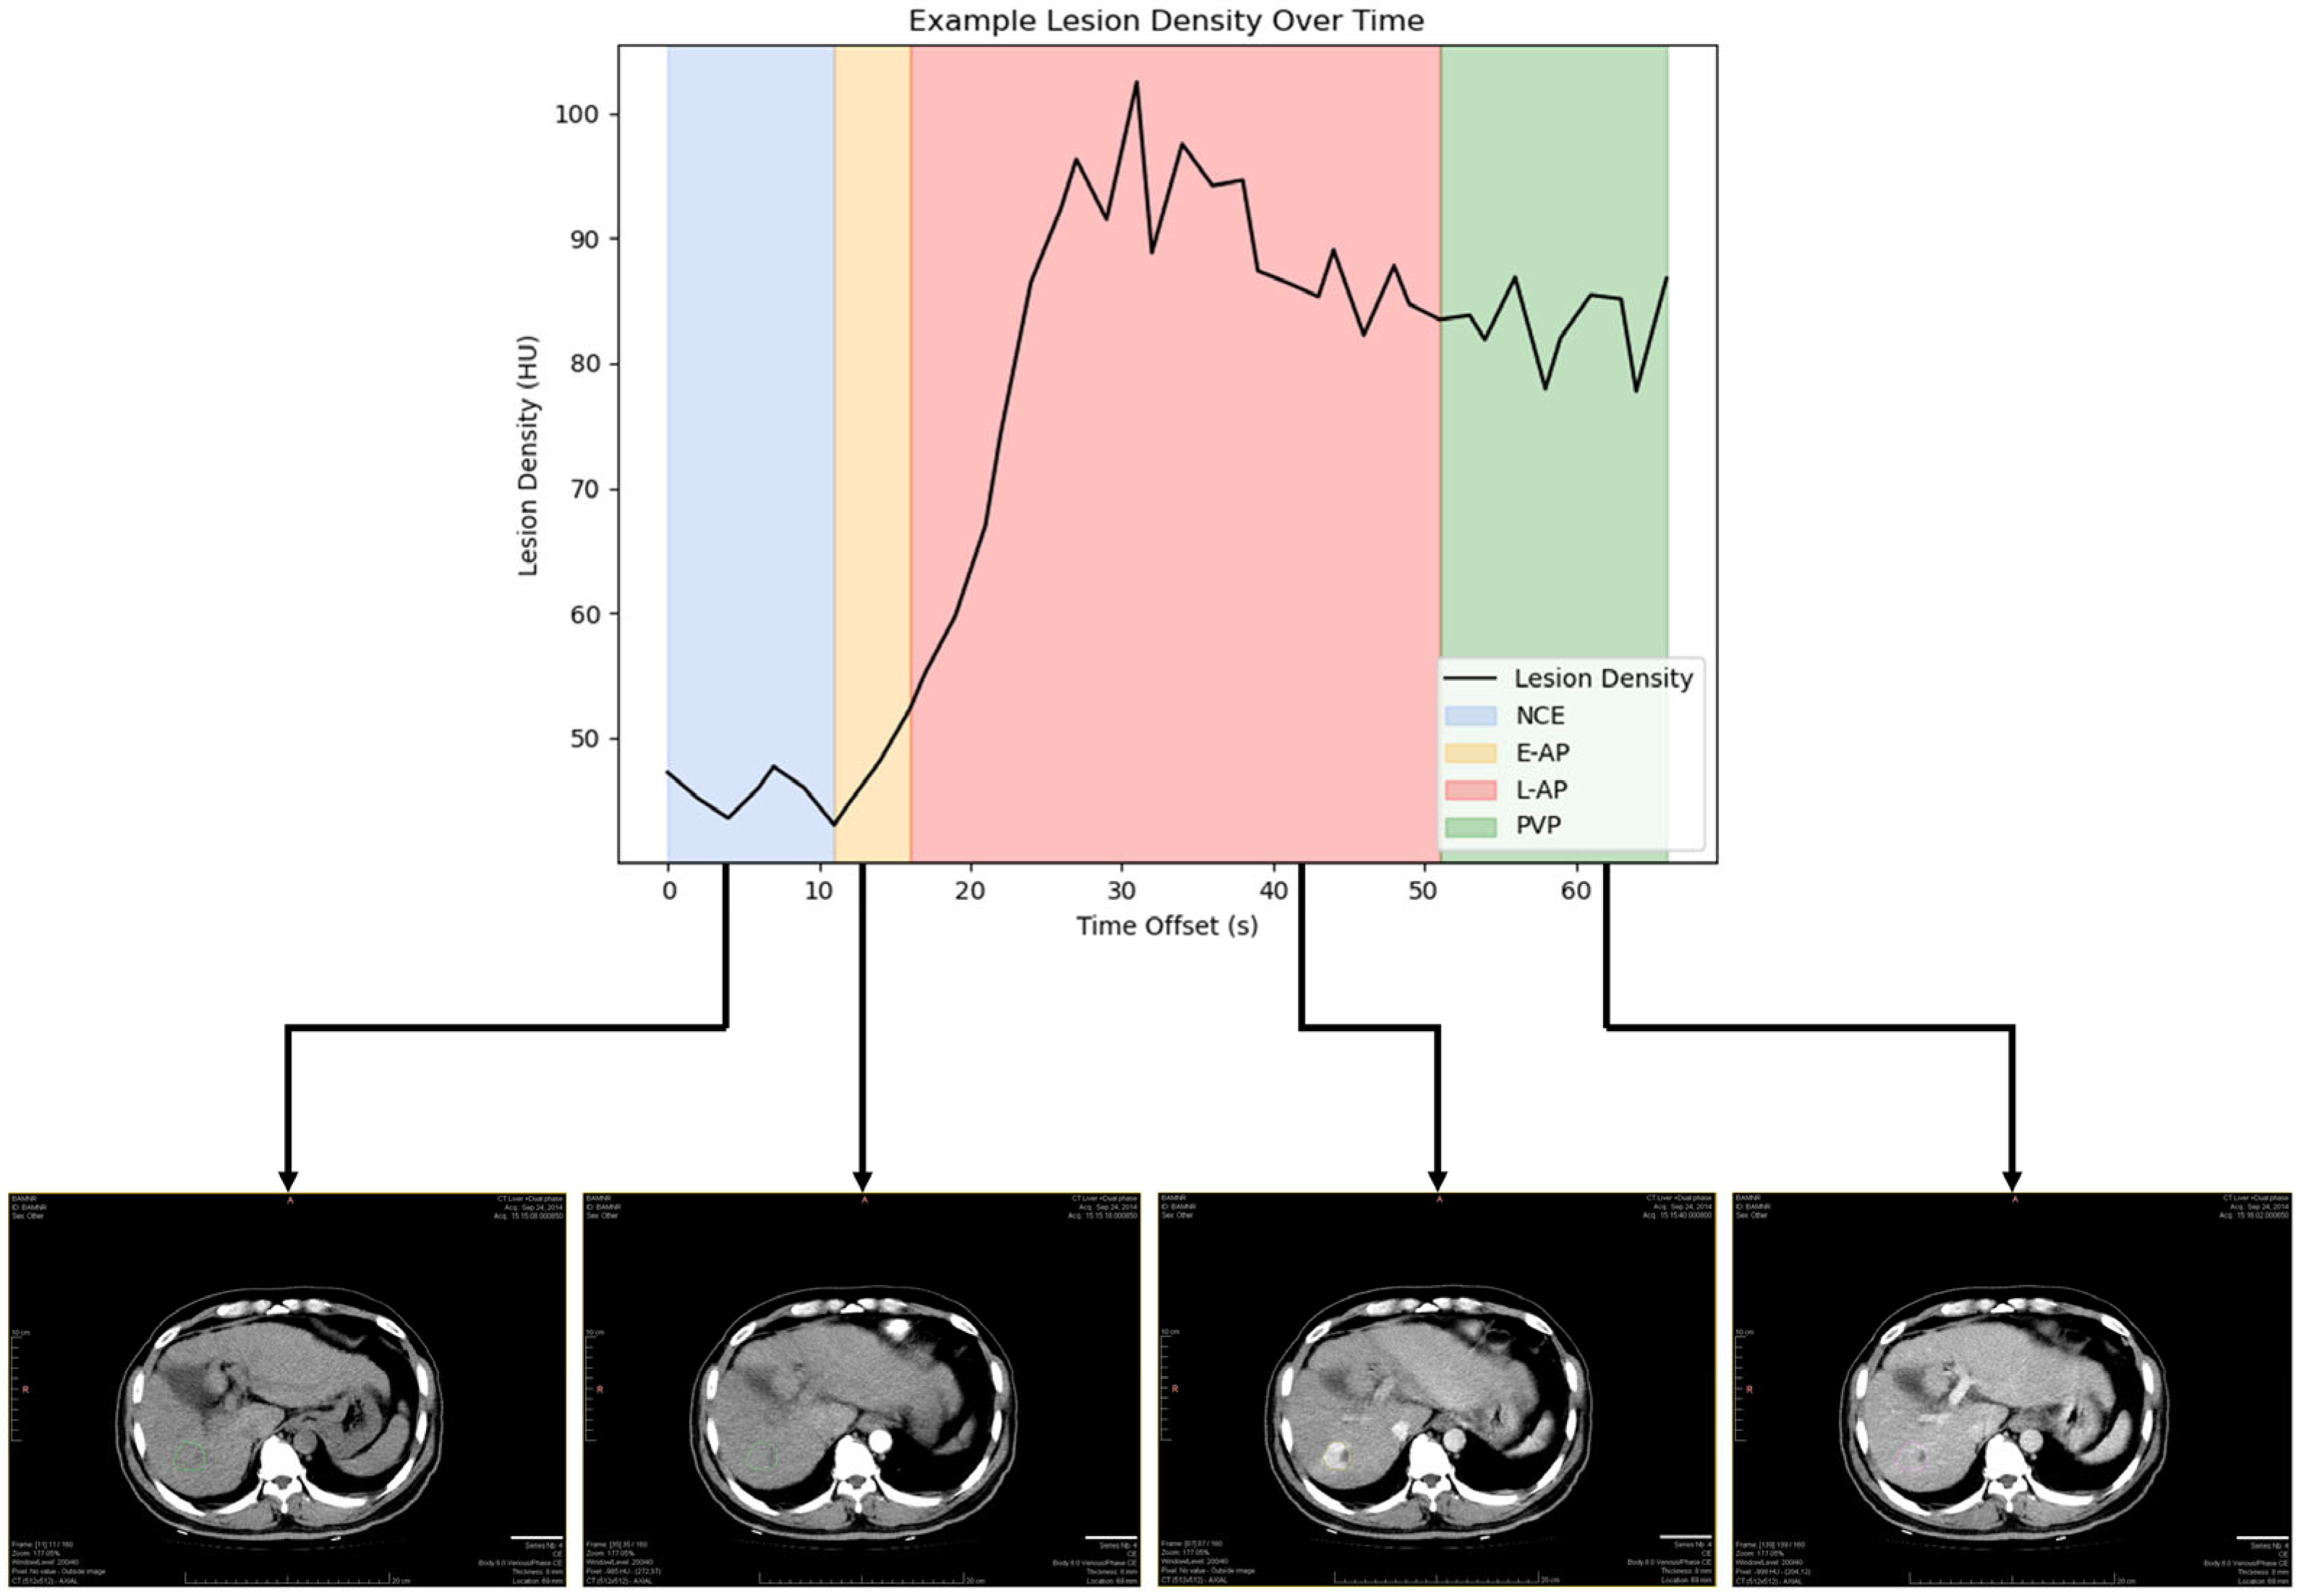

2.2. Reference Standard for Contrast Enhancement Phases

2.3. Lesion Segmentation and Measurements

| Phase | Coefficient of Variance (CV) | Standard Deviation (HU) | Example Tumor | ||

|---|---|---|---|---|---|

| Mean Density (HU) | Range as a Result of Variability (HU) | % Change as a Result of Variability | |||

| All | 26.19% (24.66–27.72%) | 15.57 | 76.41 | 34.8–118.0 | ±54 |

| NCE | 9.62% (7.15–12.09%) | 9.73 | 45.03 | 36.4–53.6 | ±19 |

| E-AP | 7.58% (6.08–9.09%) | 10.59 | 44.25 | 37.1–51.5 | ±16 |

| L-AP | 22.84% (21.48–24.20%) | 18.93 | 77.96 | 41.6–114.4 | ±47 |

| PVP | 7.83% (6.76–8.89%) | 16.68 | 88.01 | 73.6–102.4 | ±16 |